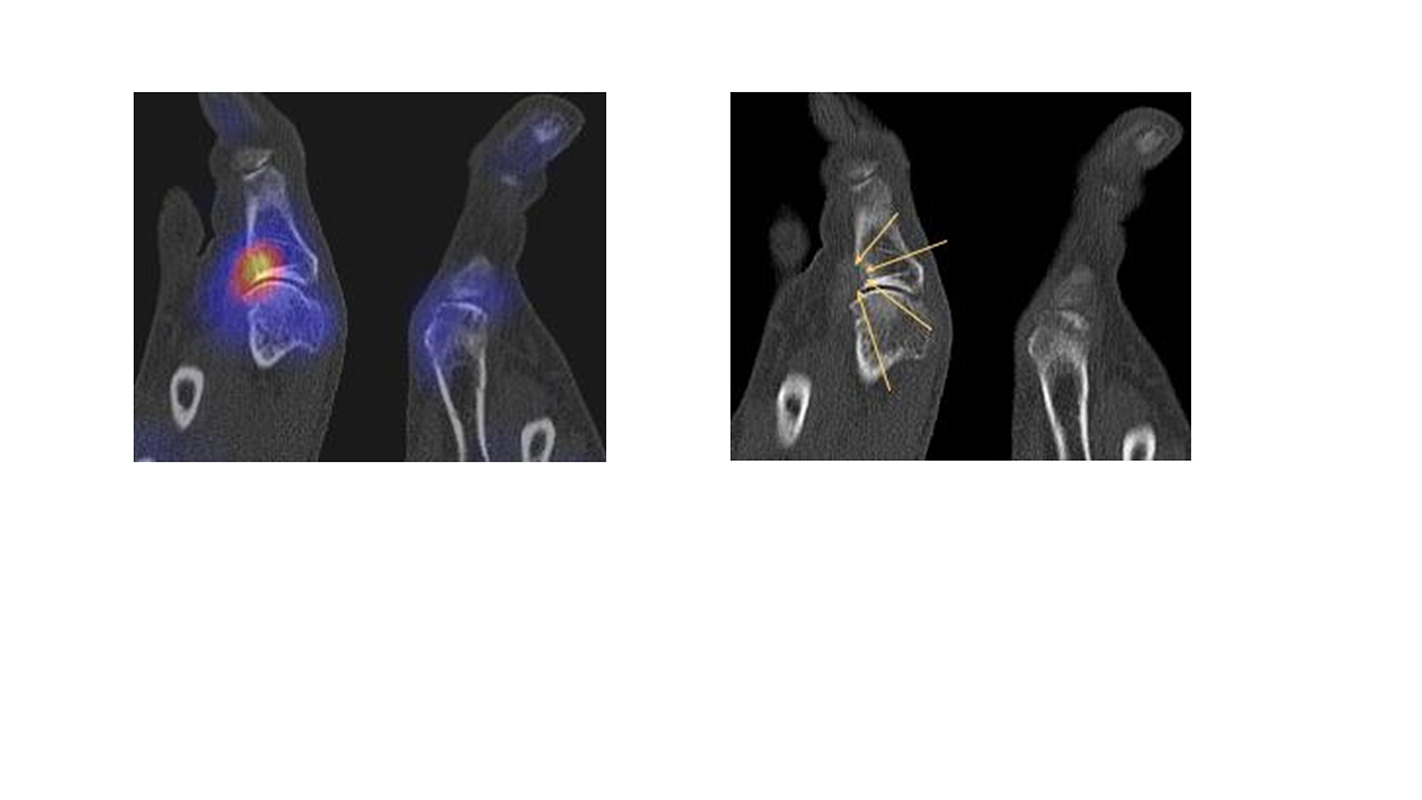

Abbildung 2.3.

Klärung bei Schmerzen im rechten OSG bei OCL an der medialen Talusschulter. Z. n. OSG-Distorsion vor 2 Jahren und Z. n. OSG-Fraktur / Syndesomosenruptur. Ausgedehnte OCL, hier jedoch kein erhöhter Knochenmetabolismus; lediglich Nachweis einer Stressreaktion im Bereich der Synchondrose eines Os trigonum als Schmerzursache.

Bei der Differenzialdiagnose von Impingement-Syndromen am Sprunggelenk kann das SPECT/CT den Ort der Symptome- verursachenden Stressreaktion darstellen 32. Eine typische Ursache für ein posteriores Impingement kann ein Os trigonum sein. Scherkräfte im Bereich der Synchondrose eines Os trigonum lösen hypermetabole Stressreaktionen aus. Die Exzision des Os trigonum stellt eine erfolgreiche Therapie dar, sodass der Befund eines szintigraphisch aktivierten Os trigonum den Erfolg einer chirurgischen Therapie vorhersagen kann 3334.

In Abbildung 3.4. ist ein typisches Beispiel für ein symptomatisches Os trigonum dargestellt.